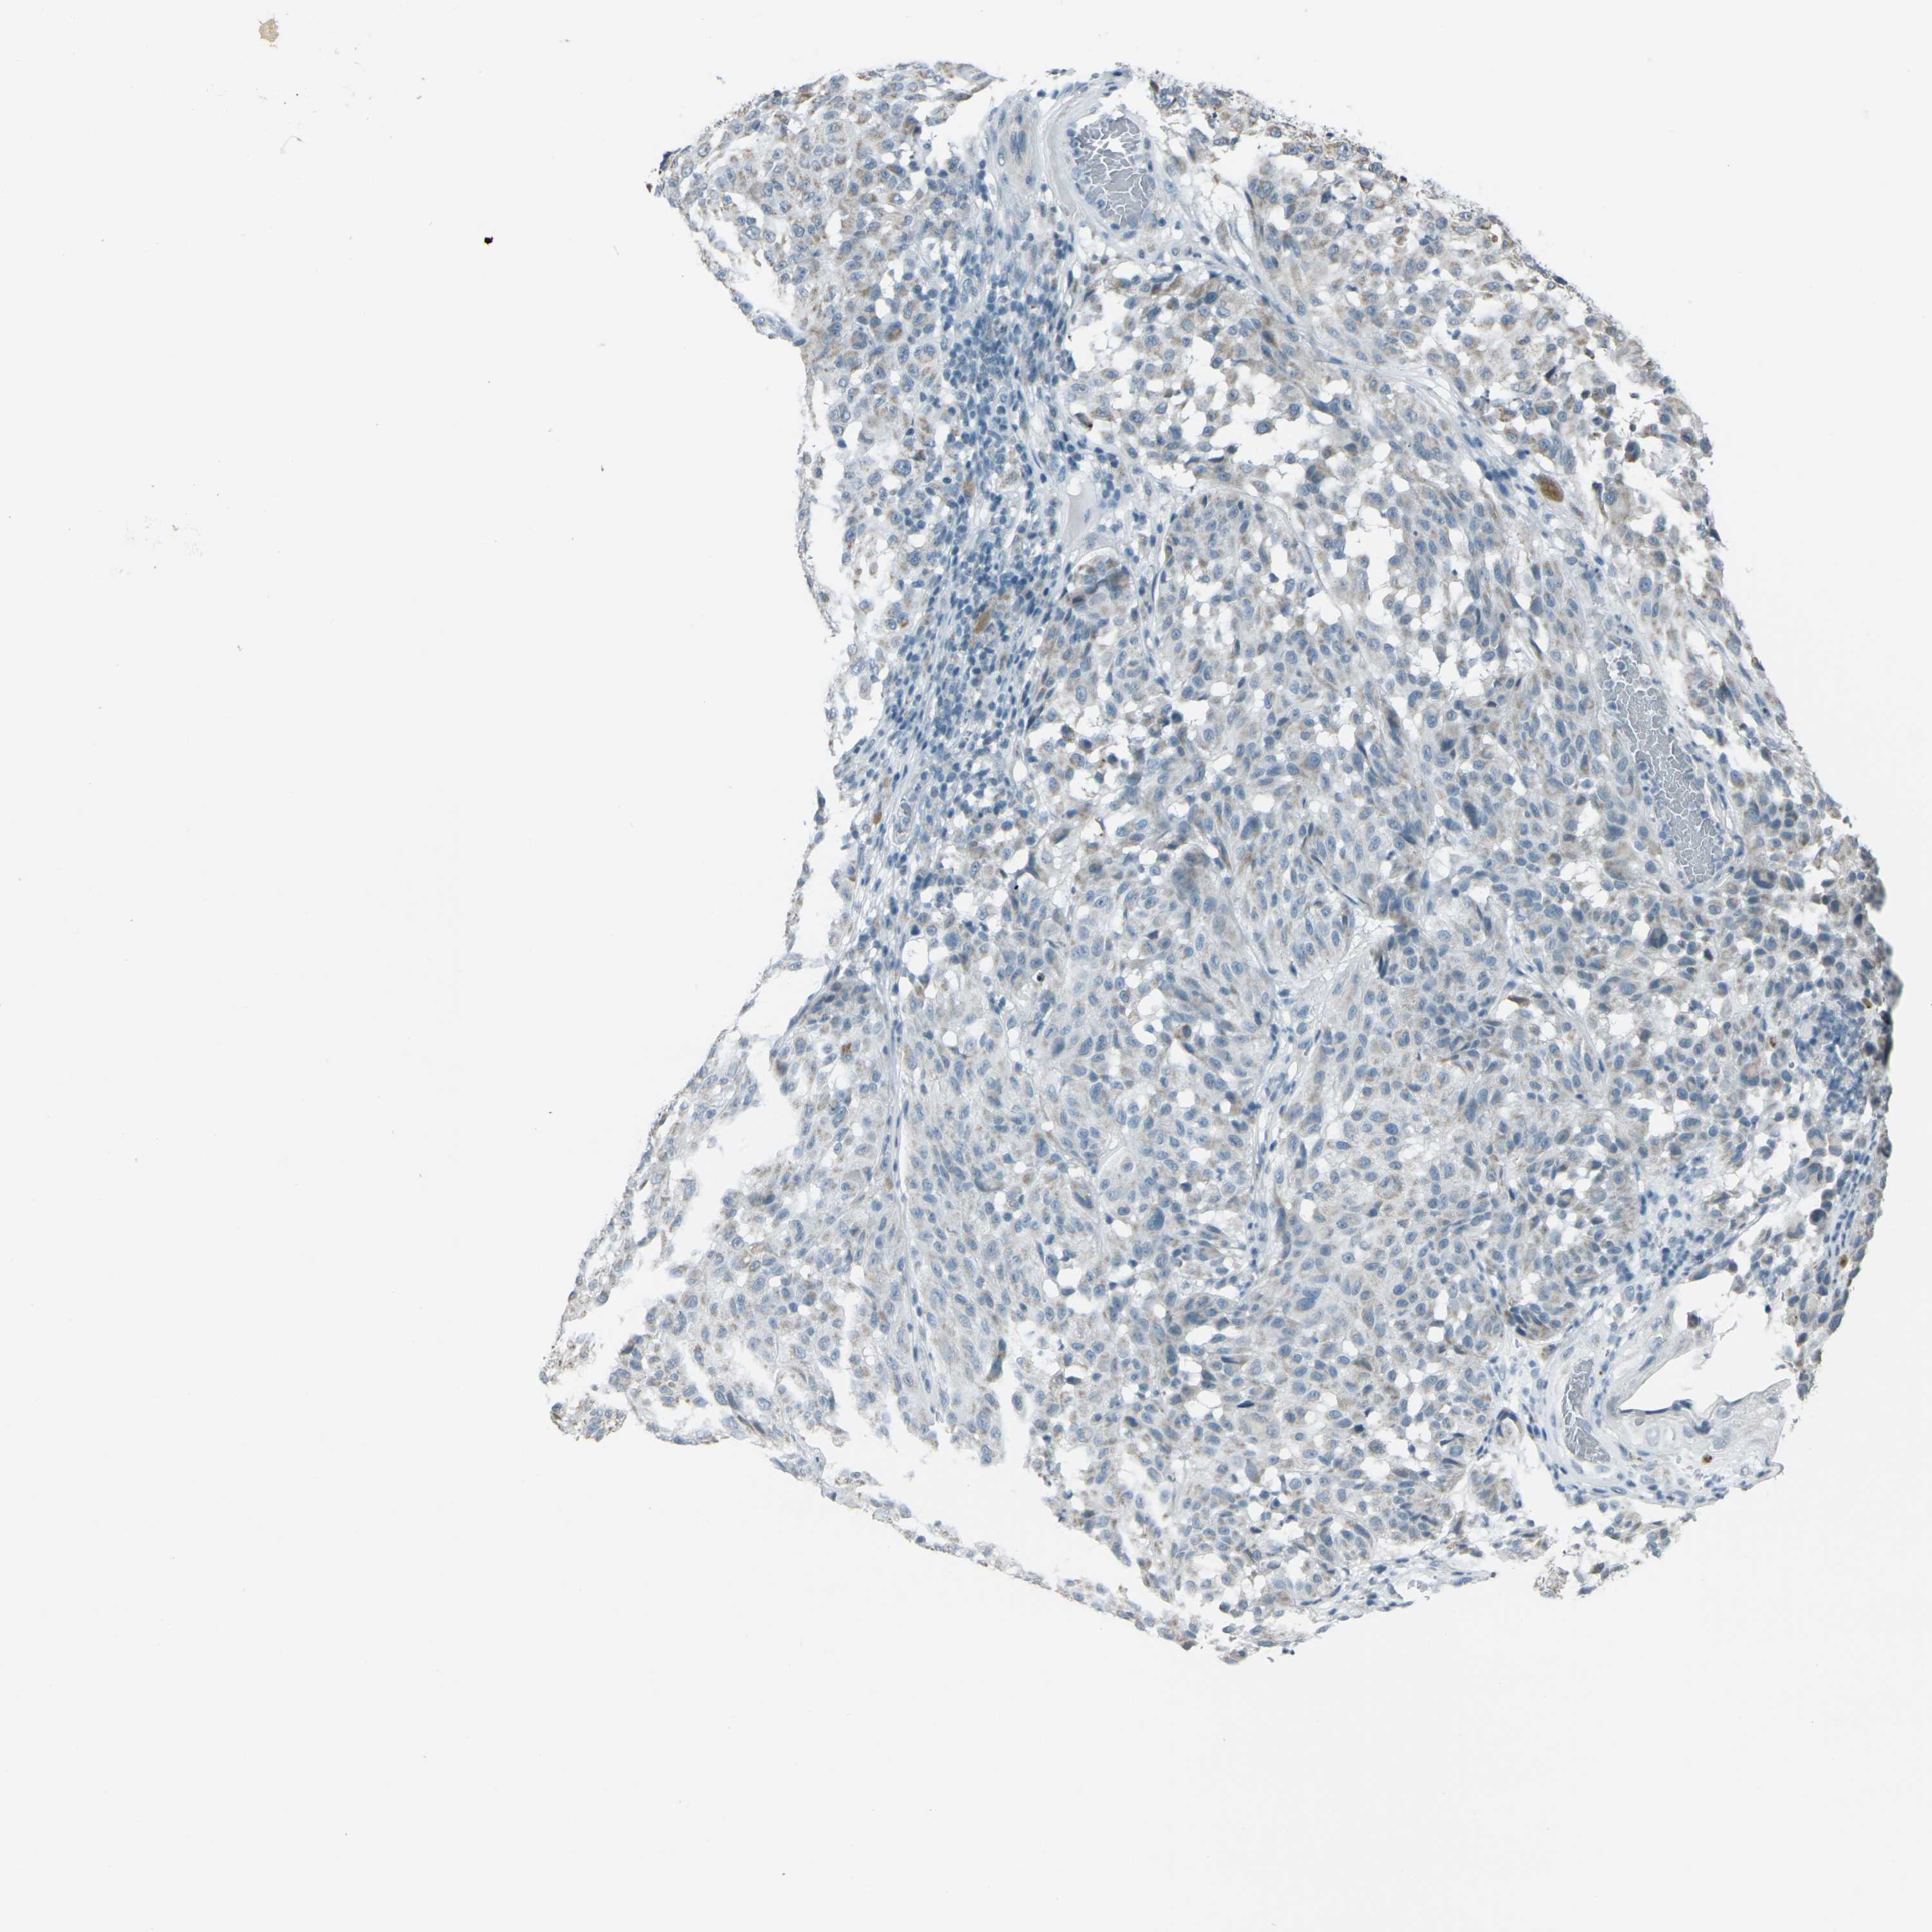

MELANOMA - Protein expressioni

A mouse-over function shows sample information and annotation data. Click on an image to view it in a full screen mode. Samples can be filtered based on level of antibody staining by selecting one or several of the following categories: high, medium, low and not detected. The assay and annotation is described here.

Note that samples used for immunohistochemistry by the Human Protein Atlas do not correspond to samples in the TCGA dataset.

Antibody stainingi

Antibody staining in the annotated cell types in the current human tissue is reported as not detected, low, medium, or high, based on conventional immunohistochemistry profiling in selected tissues. This score is based on the combination of the staining intensity and fraction of stained cells.

Each image is clickable and will lead to virtual microscopy that enables deeper exploration of all samples and also displays staining intensity scores, fraction scores and subcellular localization as well as patient and tissue information for each sample.

Antibody HPA042205

Antibody HPA043013

Antibody CAB011603

Staining

High

Medium

Low

Not detected

Intensity

Strong

Moderate

Weak

Negative

Quantity

>75%

75%-25%

<25%

None

Location

Nuclear

Cytoplasmic/membranous

Cytoplasmic/membranous,nuclear

Malignant melanoma, NOS

Malignant melanoma, Metastatic site

Malignant melanoma in situ